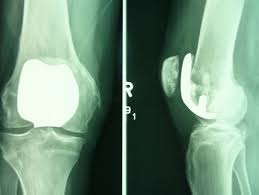

인공관절 수술은 원리에 따라 다양하게 나뉘며 닳아 없어진 무릎 연골 대신 인체에 해가 없는 코발트크롬, 티타늄합금 등의 금속이나 세라믹으로 만들어진 인공관절을 삽입하는 과정으로 진행된다고 한다. 다만 환자 입장에선 자신에게 적합한 수술법을 찾는 것이 더욱 중요해졌다고 한다.

3D 맞춤형 인공관절 수술은 다음의 과정으로 진행된다고 한다. 먼저 수술 1~2주 전 무릎 MRI 검사를 통해 무릎관절의 모양•크기 등 구조를 측정한다고 한다.

그리고 3D 시뮬레이션으로 가상 수술을 집도해 인공관절을 어디에 어느 각도로 넣을지를 분석한다고 한다. 이를 기반으로 환자 개인의 맞춤형 수술 도구를 3D프린터로 전송해 출력한다고 한다.

완성된 출력물 즉, 관절 절삭 부위를 알려주는 ‘PSI(Patient Specific Instrument)’라는 절삭유도장치라고 한다. 수술 시 손상된 관절 부위에 PSI를 끼우고 망가진 관절을 잘라내면 인공관절이 정확한 자리에 이식된다고 한다.